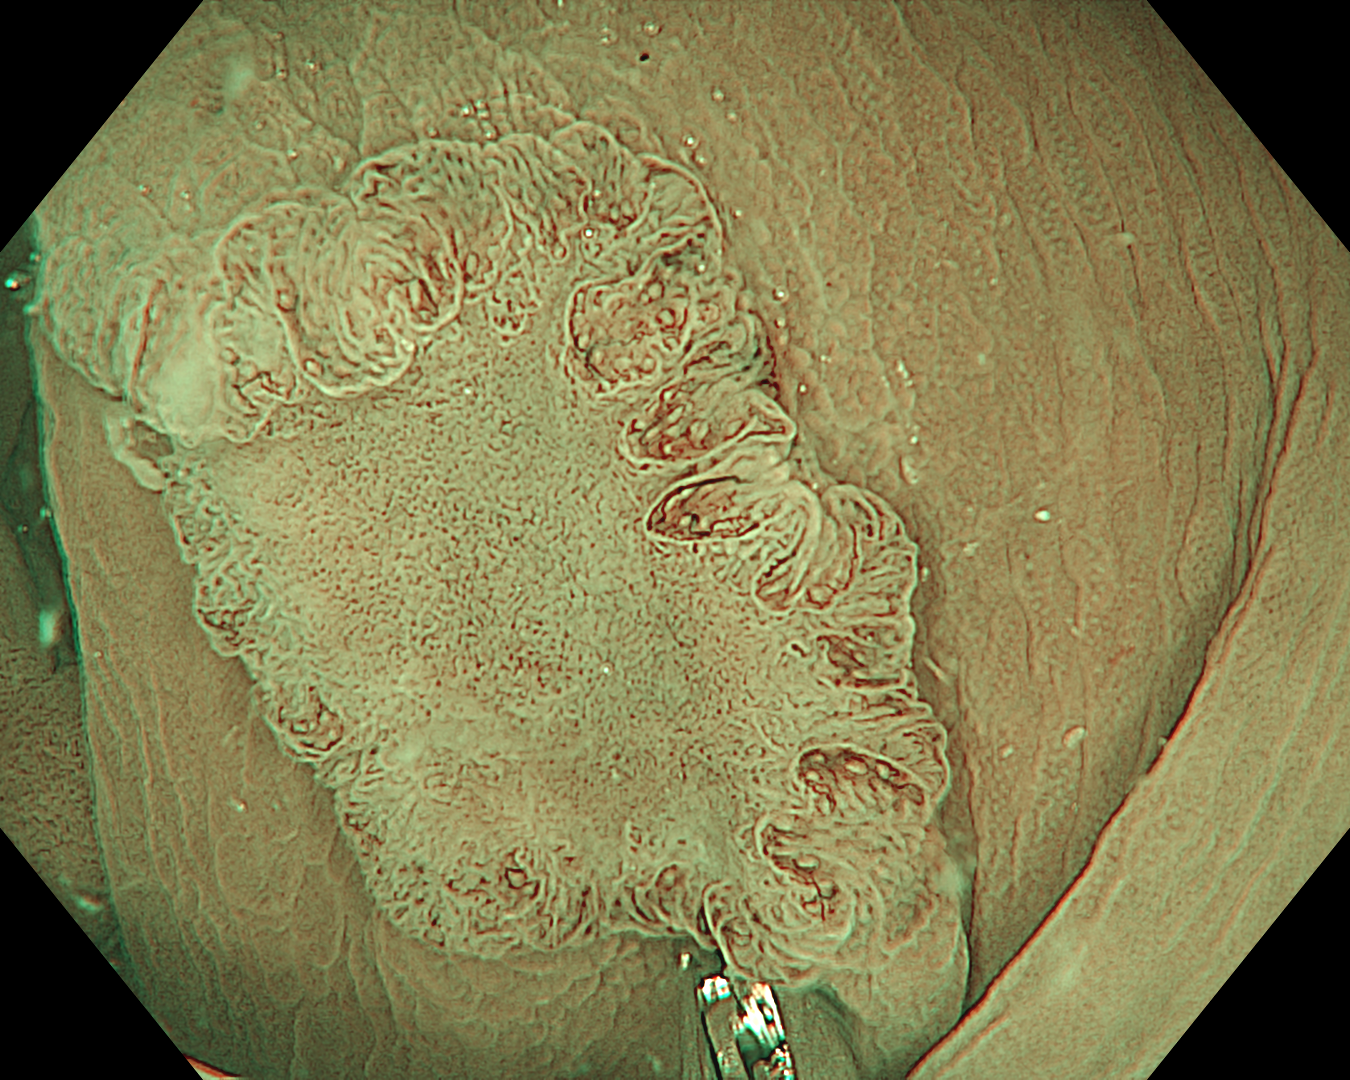

3. Near Focus mode with NBI

The lesion can be diagnosed as type JNET 2b in JNET classification. Endocuff helps reveal the entire colon mucosa better, especially the locations behind the mucosal folds. Endocuff also helps reveal lesions better for observation.

4. Near Focus mode with NBI

5. Near Focus mode with NBI

This is a LST-NG-PD with a 16-mm diameter. The lesion has a red O-ring with a depressed area about 14mm in diameter. In “air” endoscopy and underwater endoscopy, the lesion has a “non-extension” or “sclerosis of the wall” sign. Observing in the “near focus” magnifying endoscopy, some areas had JNET type 2b, suggesting that this is either an intramucosal cancer lesion or a cancer lesion with submucosal invasion.